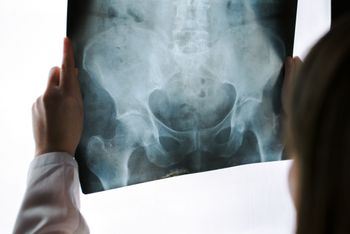

Delays in diagnosing axSpA are troubling, write the authors of a report in the journal Rheumatology. Delays of up to 10 years have been reported. Not all physicians may be familiar with the signs and symptoms of axSpA.

T1-weighted MRI may be a highly specific and reliable test for diagnosing SpA.

Recent studies assessed the impact of statins on disease activity and compared plain radiography vs MRI for early diagnosis of axSpA.